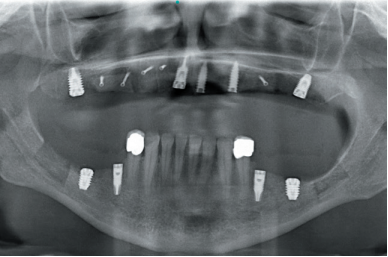

Four months after the initial regeneration of the maxilla surgery a new dental cone-beam is performed, in which the next surgery phase is planned based on the bone gain that has been achieved with the block grafts and the Split technique in two phases. In the images we can see how in the maximum atrophy areas, where the blocks are placed a width has been achieved that triples the initial width (Figures 19 and 20). At the flap opening it is seen as the planification CT images correspond to reality, and also that the area treated by Split in two phases has achieved a crest width that now allows the removal of the transitional implants and the insertion of the new implants in this position, with a better starting and axis situation for the subsequent construction of the prosthesis (Figures 21-22). The implants are inserted and a temporary prosthesis of progressive load is made supported on the implants placed in the first surgical phase. In this way, the patient can have a fixed prosthesis on

implants that will serve to shape the provisional ones in terms of aesthetics and function before the final prosthesis (Figures 23-24).

After four months the loading of the inserted implants in this second surgical phase is carried out. Again, a second provisional prosthesis of progressive loading is chosen, elaborated in the same way as the previous ones. three months aft er the occlusion is prepared for the manufacture of the fi nal prosthesis, so the prosthesis is transformed into a metal-ceramic prosthesis, screwed on transepithelial made by CAD-CAM (Figures 25-26).

The pati ent has recovered the requested functi on, as well as the correction of the occlusion of the complete prosthesis, which presented a right lateral cross bite with decrease in the vertical dimension at the beginning of the treatment. The patient comes to her review and the treatment remains stable as shown in the images taken after 10 years of follow-up (Figures 27-28).